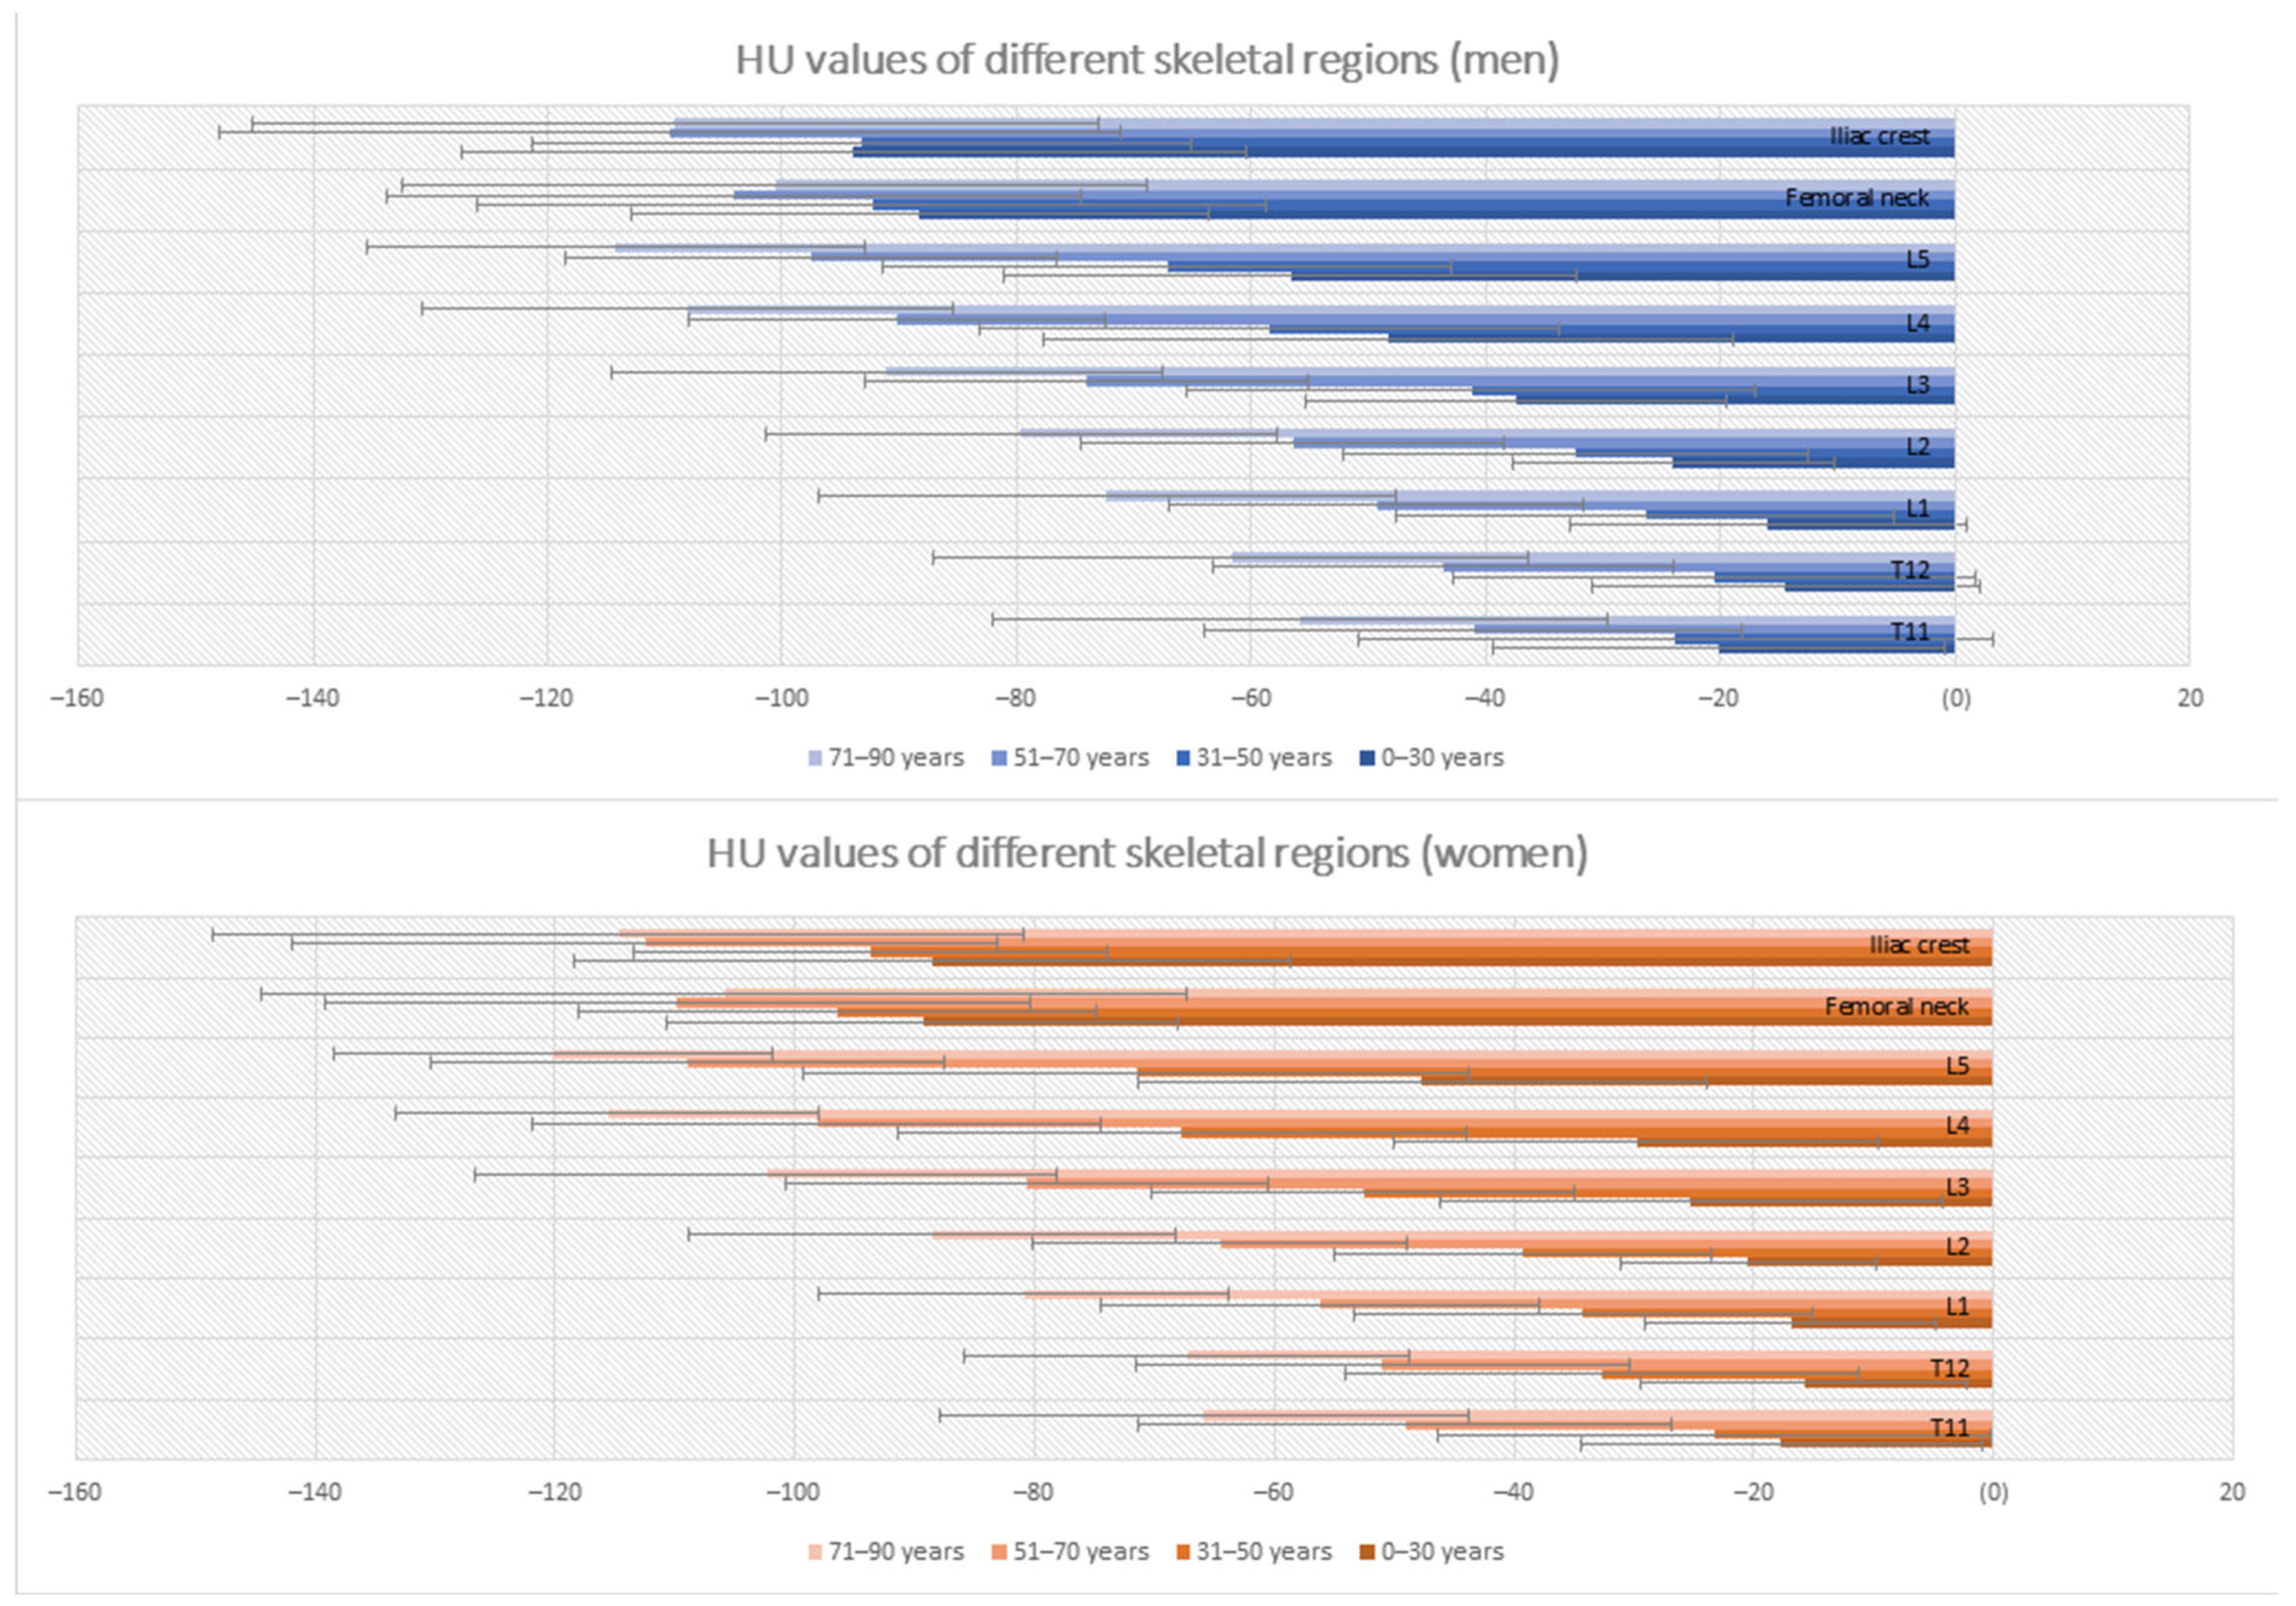

3.2. Differences in Bone Marrow Attenuation by Age and Gender

| 0–30 Years | 31–50 Years | 51–70 Years | 71–90 Years | |||||

|---|---|---|---|---|---|---|---|---|

| Vertebral Body | Men | Women | Men | Women | Men | Women | Men | Women |

| T11 | −20.15 ± 19.27 | −17.73 ± 16.73 | −23.81 ± 27.07 | −23.32 ± 23.06 | −42.05 ± 22.93 | −49.11 ± 22.28 | −55.83 ± 26.25 | −65.86 ± 22.08 |

| T12 | −14.44 ± 16.52 | −15.85 ± 13.67 | −20.53 ± 22.23 | −32.74 ± 21.42 | −43.61 ± 19.60 | −50.99 ± 20.62 | −61.72 ± 25.41 | −67.30 ± 18.61 |

| L1 | −15.93 ± 16.88 | −16.93 ± 12.10 | −26.41 ± 21.26 | −34.31 ± 19.13 | −49.32 ± 17.65 | −56.20 ± 18.36 | −72.30 ± 24.59 | −80.92 ± 17.18 |

| L2 | −24.00 ± 13.79 | −20.45 ± 10.74 | −32.41 ± 19.82 | −39.27 ± 15.75 | −56.42 ± 18.03 | −64.55 ± 15.58 | −79.63 ± 21.81 | −88.59 ± 20.30 |

| L3 | −37.42 ± 17.91 | −25.23 ± 20.92 | −41.26 ± 24.18 | −52.56 ± 17.64 | −74.12 ± 18.87 | −80.59 ± 20.10 | −91.10 ± 23.44 | −102.43 ± 24.28 |

| L4 | −48.35 ± 29.41 | −29.75 ± 20.21 | −58.43 ± 24.69 | −67.77 ± 23.72 | −90.17 ± 17.77 | −98.20 ± 23.70 | −108.04 ± 22.65 | −115.61 ± 17.62 |

| L5 | −56.62 ± 24.43 | −47.70 ± 23.72 | −67.13 ± 24.23 | −71.54 ± 27.81 | −97.51 ± 20.91 | −108.97 ± 21.40 | −114.92 ± 21.21 | −120.16 ± 18.28 |

| Femoral neck * | −88.27 ± 24.54 | −89.36 ± 21.28 | −92.37 ± 33.67 | −96.52 ± 21.62 | −104.18 ± 29.59 | −109.80 ± 29.42 | −100.62 ± 31.75 | −105.92 ± 38.65 |

| Iliac crest | −93.90 ± 33.42 | −88.50 ± 29.89 | −93.19 ± 28.10 | −93,71 ± 19.18 | −109.60 ± 38.45 | −112.47 ± 29.40 | −109.14 ± 36.03 | −114.73 ± 33.86 |